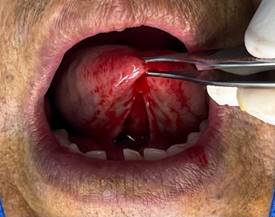

· Desprendimiento nítido del frenillo: Al terminar la primera fase de la diéresis se debe observar el desprendimiento nítido de la inserción del frenillo. Con este desprendimiento se intenta evitar la recidiva. (Figura 5)

Figura 5. Desprendimiento nítido del frenillo.

Elaboración: Los autores.

· Disección y eliminación del frenillo: Se utiliza un elevador o tijeras quirúrgicas para separar y disecar el frenillo del tejido circundante. Se corta el frenillo en su base y se retira por completo. (Figura 6)

Figura 6. Disección y eliminación del frenillo.